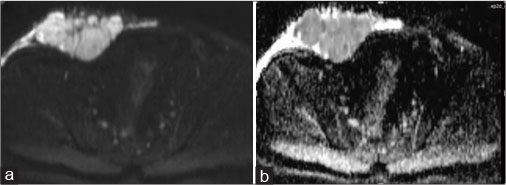

A 40-year old male patient presented with swelling over the anterior abdominal wall on the right side in lower abdomen for 1 month which was rapidly increasing in size. There was a history of weight loss. The mass was painless. The ultrasonography showed a large, well-defined solid mass with lobulated outlines in anterior abdominal wall in the right paraumbilical and hypogastric region [Figure 1]. The mass was seen in the subcutaneous plane, causing extrinsic compression on adjoining right rectus abdominis and external oblique muscle. It was predominantly hypoechoic with small areas of the necrosis in its center and showed mild vascularity on color Doppler. No calcification was seen. Plain and contrast enhanced computed tomography (CT)-scan of the abdomen and pelvis was performed. A large, well defined solid mass with lobulated outline measuring approximately 96 mm × 38 mm × 98 mm in transverse, anteroposterior and craniocaudal dimension was noted in the anterior abdominal wall on the right side in right iliac region extending to hypogastric region. It was slightly hypodense with respect to muscle on the plain study with a CT value of 35–45 HU and showed a mild heterogeneous enhancement in contrast study (CT value 55–65 HU). No calcification was noted. The mass was in subcutaneous plane and was extending anteriorly up the skin. Posteriorly, it was causing mass effect on the right rectus abdominus and adjoining external oblique and internal oblique muscles which were compressed and displaced posteriorly with obliteration of intervening fat planes [Figure 2]. An enhancing vessel was noted in the right rectus abdominus extending into the mass suggestive of neovascularity. No intra-abdominal extension was noted. Rest of the abdominal wall appeared normal. No hepatic or adrenal metastases, intra-abdominal lymphadenopathy noted. On magnetic resonance imaging (MRI), the mass appeared slightly hyperintense with respect to muscle on T1-weighted image, heterogeneously hyperintense on T2-weighted image (T2WI), and hyperintense on short tau inversion recovery and showed restricted diffusion on diffusion-weighted imaging with low apparent diffusion coefficient (ADC) values (ADC = 800). It was causing mass effect on the right rectus abdominus and adjoining external oblique and internal oblique muscles [Figure 3] [4] [5] [6].

| Figure 3: Magnetic resonance imaging of the abdomen - axial T1 (a), axial T2 (b-d) showing well-definedsolid mass with lobulated outlines in the right iliac fossa and hypogastric region in subcutaneous plane causing extrinsic compression and posterior displacement of abdominal wall muscles appearing slightly hyperintense on the T1-weighted image and hyperintense on T2-weighted image